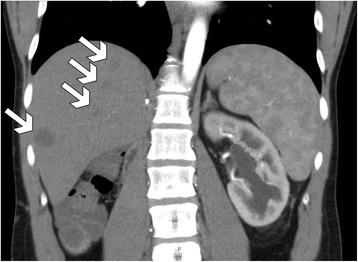

A 28-year-old male patient with gross hematuria and right flank pain was diagnosed with right kidney tumor penetrating to IVC. Preoperatively, acute distal thrombosis in inferior vena cava and lower extremities veins occurred. Right radical nephrectomy with tumor thrombectomy via cavotomy was performed. In order to prevent pulmonary embolism, IVC was ligated below left renal vein level. Histopathological examination revealed a triphasic nephroblastoma without anaplastic features. Postoperatively, patient was diagnosed with metastatic liver disease, which was treated with two lines of chemotherapy followed by radiotherapy with achievement of complete response.

一名 28 岁男性患者因肉眼血尿和右侧腰痛被诊断为右肾肿瘤穿透 IVC。术前发生急性 IVC 远端和下肢静脉血栓形成。通过腔静脉切开术进行了右肾根治性切除术和肿瘤血栓切除术。为了预防肺栓塞,在左肾静脉水平以下结扎 IVC。组织病理学检查显示为三时相肾母细胞瘤,无间变特征。术后患者被诊断为肝转移疾病,接受了两线化疗和放疗,达到完全缓解。